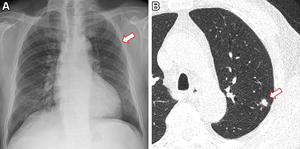

image: Images in a 60-year-old woman who underwent chest radiography for health checkup purposes and was allocated to the artificial intelligence (AI) group. (A) Frontal chest radiograph shows a subtle nodular opacity (arrow) in the right middle lung zone. (B) The lesion was detected by the AI-based computer-aided detection software, with an abnormality probability of 81.1%. The designated radiologist reported this chest radiograph as positive. (C) Axial, noncontrast, low-dose chest CT scan shows a 1.1-cm solid nodule (arrow) in the right lower lobe. The patient underwent percutaneous needle biopsy, and the nodule was confirmed to be adenocarcinoma. view more